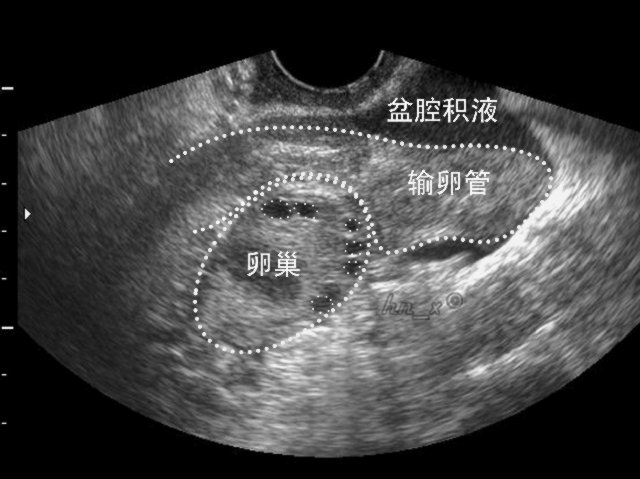

盆腔积液的超声图像

在正常情况下,腹膜具有吸收和分泌的功能,使腹膜腔内存在少许浆液,以减少腹腔脏器间的摩擦。而这些浆液通过脏器间的摩擦后,往往会积聚在腹腔最低的部位——盆腔;在B超检查报告上,则会将这最低的部位详细描述为“子宫直肠窝”或“子宫直肠陷窝”(由腹膜围绕着直肠前壁向下移行于阴道后穹隆,再向前向上移行覆盖子宫颈和子宫后壁,形成了直肠和子宫之间的腹膜凹陷)。所以,当女性平卧做B超检查时,盆腔内有少许积液是正常现象。

另外,由于卵巢表面是没有腹膜覆盖的,在正常情况下,两边的卵巢每个月会轮流排卵。当卵巢的优势卵泡破裂时就会把卵泡液排进腹腔,从而集聚在子宫直肠窝,少则形成2~3毫升,多则10毫升。同样,每一个月月经来潮时,少量经血和子宫内膜碎屑也可以从子宫腔里逆流进入输卵管,从而“倒流”入腹腔内,最后再往腹腔最低处的盆腔处汇聚成积液。